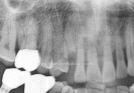

Clinical Cases

• Case1

• Case2

• Case3

• Case4

• Case5

• Case6

• Case7

• Case8

• Case9

• Case10